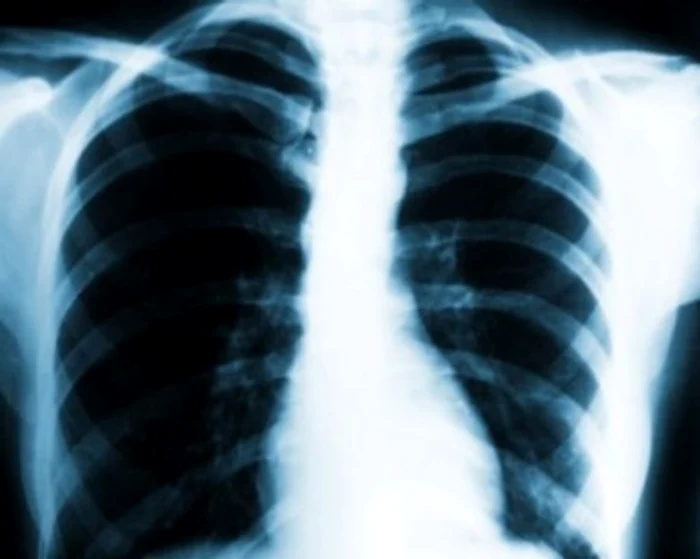

Organizaţia Mondială a Sănătăţii avertizează că tuberculoza este încă foarte răspândită în multe ţări, astfel că la fiecare patru secunde un om este diagnosticat cu această maladie, iar la fiecare zece secunde un bolnav moare din cauza TBC. Aproape 80% dintre bolnavii de tuberculoză au vârste de 15 - 45 de ani.

În România, sunt înregistrate anual 27.500 cazuri noi, iar peste 100.000 sunt rude ale celorbolnavi care fac acestă maladie. În ultimul deceniu, peste 1.000.000 de români au venit în contact cu această boală, care se transmite dacă persoana sănătoasă stă în acelaşi spaţiu închis cu bolnavul care tuşeşte cel puţin opt ore continuu.

Tuberculoza se manifestă cel mai frecvent prin tuse seacă, ce durează mai mult de trei săptămâni, febră scăzută (37-38 grade Celsius), scădere în greutate, oboseală şi transpiraţie, mai ales în cursul nopţii.